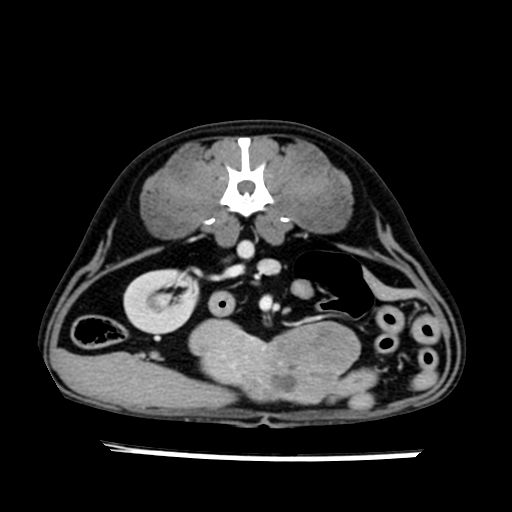

prescritto esame TAC

sequenza immagini limitata al fegato reni e surreni

le immagini ecografiche rispetto alla tac datano circa 7 mesi prima ,le surrenali sono normali nonostante il test acth sia risultato positivo .all’esame TAC dopo diversi mesi risultano aumentate armonicamente nel volume e si individua un forte sospetto di adenoma ipofisario .

sospetto adenoma ipofisario vs. meno probabilmente meningioma della base; intertiziopatia polmonare; lesione espansiva epatica, verosimilmente del lobo laterale sinistro, di sospetta natura neoplastica; lesioni spleniche di natura da definire; iperplasia/ipertrofia delle ghiandole surrenali, bilateralmente; vertebra di transizione del rachide toracico; tenosinovite cronica del muscolo bicipite brachiale di destra.